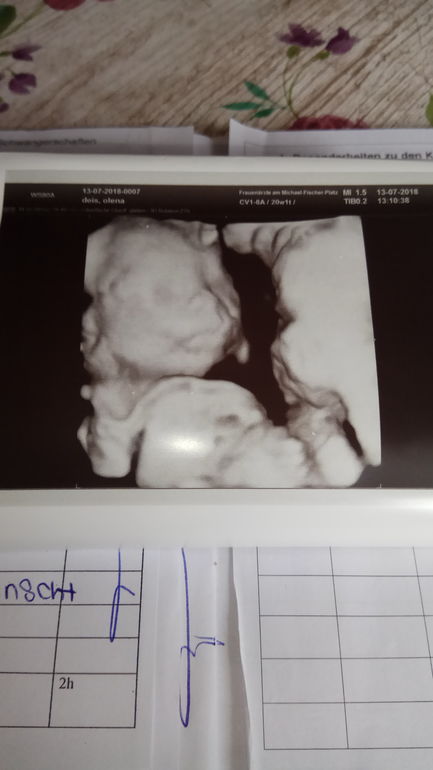

Сегодня прошли 2 скриннинг всё соответствует сроку и работает как надо 😁

Врач всё расмотрел и показал нам.

В. У вас Мальчик

В. Вот посмотрите (пренадлежности на весь экран)😂👍